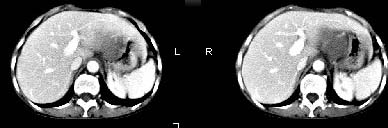

女:61岁.腹痛腹胀20天,行b超腹膜后实性占位.扫完后我查体发现患者右颈根部约3厘米类圆性包块,有移动{我考虑右颈根部包块是肿大淋巴结}.

ct:肝胃之间、胰头后、腹主a周围,融合而成团块状影,包绕血管,胰腺前移后缘分界欠清,与肝胃分界清,肿块未见明显强化,肝右叶后段小囊肿。

女:61岁.腹痛腹胀20天,行b超腹膜后实性占位.扫完后我查体发现患者右颈根部约3厘米类圆性包块,有移动{考虑右颈根部包块是肿大淋巴结}.

诊断:淋巴瘤>转移瘤。

肝胃之间、肝十二指肠韧带,胰头后、腹主a周围,融合而成团块状影,包绕血管[腹腔干、肠系膜上动脉,腹主动脉],胰腺前移后缘分界欠清,与肝胃分界清,肿块未见明显强化,肝右叶后段小囊肿。

考虑1淋巴瘤。2转移瘤。3恶性组织细胞瘤。